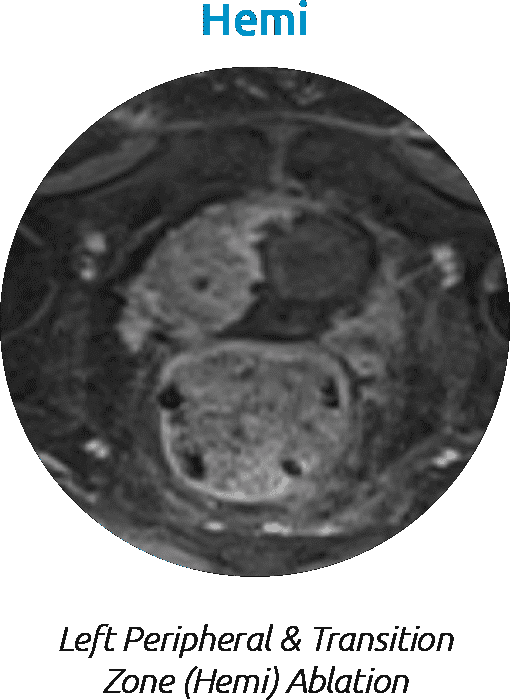

In Action: Water Vapor Ablation

Water vapor transfers energy convectively through the target prostate tissue, while respecting the natural boundaries of the prostate. Here are a few examples of water vapor ablation in different areas in the prostate.